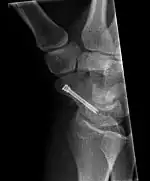

![]() The left scaphoid bone | |

The scaphoid can be slow to heal because of the limited circulation to the bone. Fractures of the scaphoid must be recognized and treated quickly, as prompt treatment by immobilization or surgical fixation increases the likelihood of the bone healing in anatomic alignment, thus avoiding mal-union or non-union.[6] Delays may compromise healing. Failure of the fracture to heal ("non-union") will lead to post-traumatic osteoarthritis of the carpus.[1]: 189 One reason for this is because of the "tenuous" blood supply to the proximal segment.[3] Even rapidly immobilized fractures may require surgical treatment, including use of a headless compression screw such as the Herbert screw to bind the two halves together.

Scaphoid fractures may be difficult to diagnose via plain x-ray. A repeat x-ray may be required at a later date, as might cross-sectional imaging via MRI or CT scan.[6]